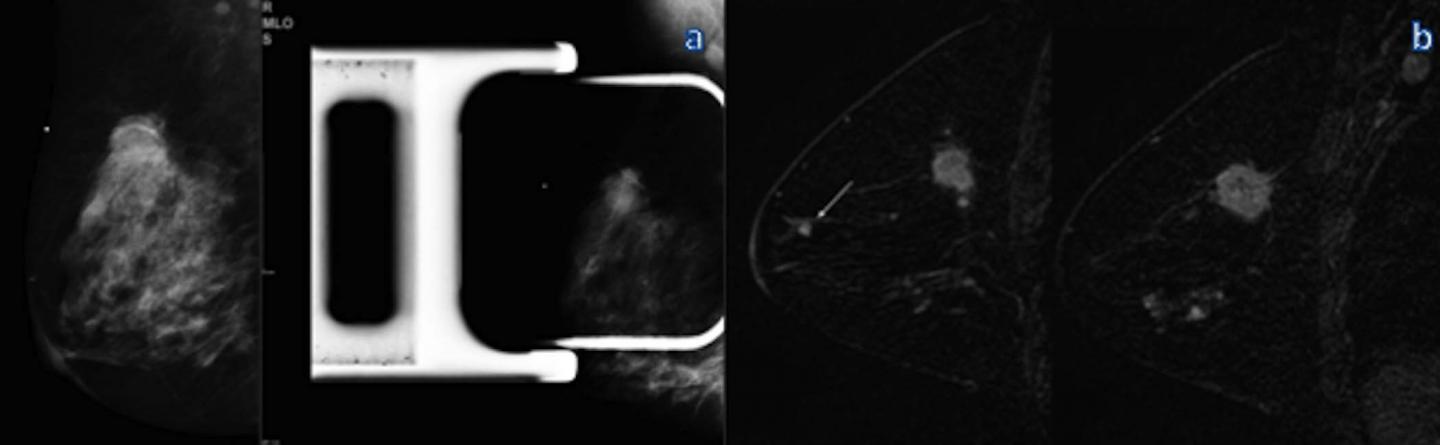

OAK BROOK, Ill. - Additional breast cancers found with MRI are sometimes larger and potentially more aggressive than those found on mammography, according to a study published online in the journal Radiology . Researchers said that in some cases MRI findings of additional cancers not seen on mammography may necessitate a change in treatment.

Breast MRI is the most sensitive technique for the detection of breast cancer, with widespread application in the screening of high-risk patients and pre-surgical planning. In younger women and women with dense breasts, MRI is effective in the detection of what are known as multicentric cancers, meaning breast cancers involving two or more distinct primary tumors, usually in different quadrants of the breast. However, there has been some debate about the clinical significance of multicentric cancers found with MRI.

In 73 of those 285 patients, or 25.6 percent, MRI identified at least one additional cancer in a different quadrant of the breast than the index cancer, or the cancer detected by mammography and/or breast palpation.

These multicentric cancers were larger than the known index cancer in 17 of the 73 patients, or 23.3 percent. In addition, the MRI-detected multicentric cancers were greater than 1 centimeter in size in 25 percent of the 73 patients.

"The results show that multicentric cancer detected on breast MRI after mammography appears to represent a larger tumor burden in approximately a quarter of patients and can result in potential changes to cancer grade and treatment," Dr. Iacconi said.